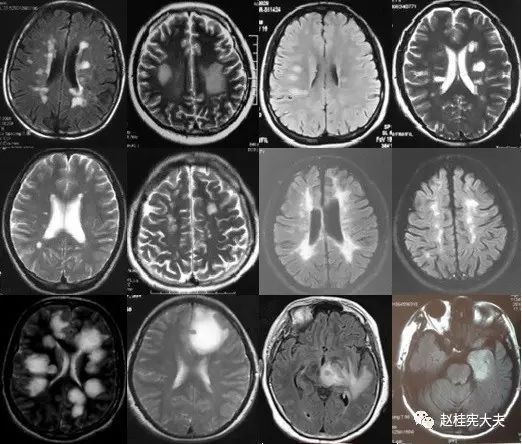

重要申明:以下每个部分会配磁共振图片,因疾病和影像之间存在同病异象、同像异病,为避免误导,图片不标注疾病,请各自鉴赏,另其中有部分图片来源于网络,有疑问可与本人联系。

I--inflammation,炎症

脱髓鞘,多发性硬化(MS)、视神经脊髓炎(NMO)、急性播散性脑脊髓炎(ADEM)、MOG相关性脱髓鞘病变、自身免疫性脑炎、CNS血管炎、神经系统结节病、Susac's Syndrome、Clippers’综合症、桥本氏脑病等。还有如急性、亚急性的放疗损伤等。

N--neoplasm,肿瘤

各种肿瘤,如胶质瘤、淋巴瘤、脑膜瘤、血管内淋巴瘤,生殖细胞瘤、各种转移瘤、心房粘液瘤等。神经纤维瘤病也可在中枢出现影像学上类似脱髓鞘的病变。